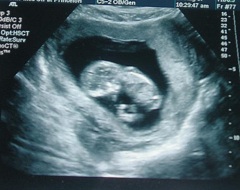

Матка по УЗИ в 9 недель беременности размерами соответствует грейпфруту. Гормональная перестройка организма приводит к улучшению внешнего вида кожи – она становится более ровной и гладкой. Для благополучного течения беременности в крови увеличивается уровень женских половых гормонов и хорионического гонадотропина.